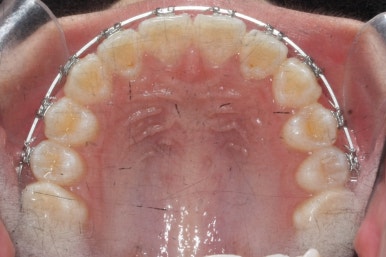

8개월이 지난 모습입니다.

장치는 앞니 4개 + 헤드기어만 사실상 했습니다. 송곳니에는 아무것도 하지 않았죠.

덧니의 변화된 모습이 느껴지시나요?

다시 한 번 말씀드리면 공간확보만 된다면 서서히 좋아지게 됩니다. 100%는 아니기 때문에 추후에 전체적으로 정리를 해줄 필요가 있는데 미리 이렇게 해두면 훨씬 추후에 작업이 간소해지죠.